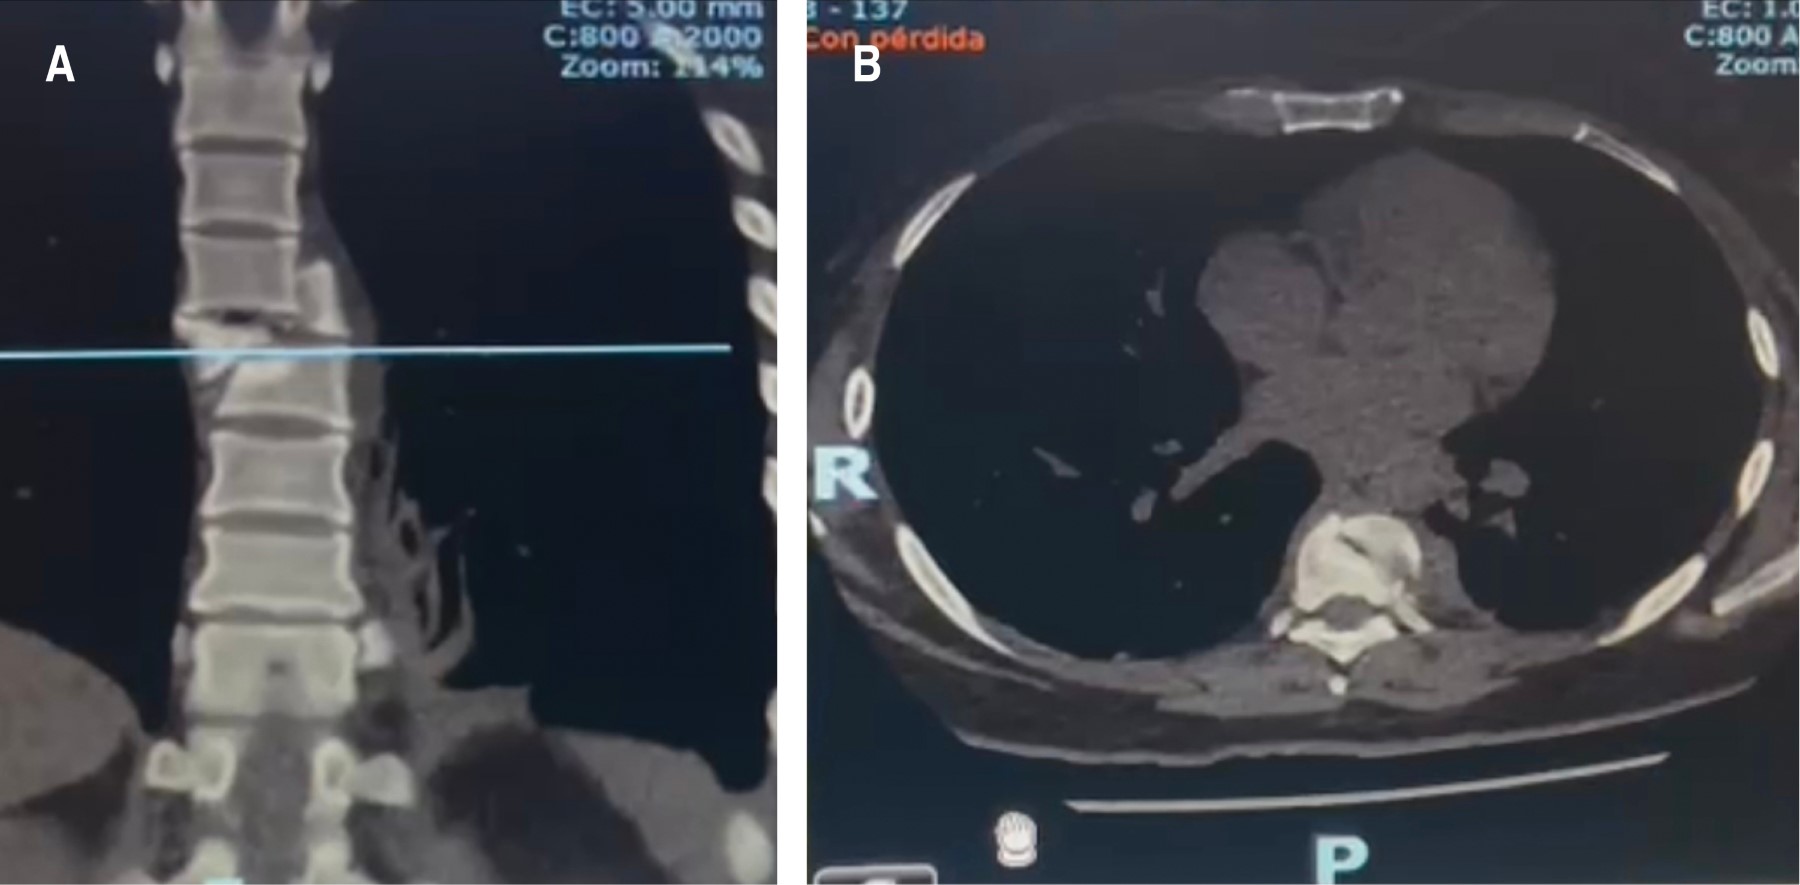

Figure 3